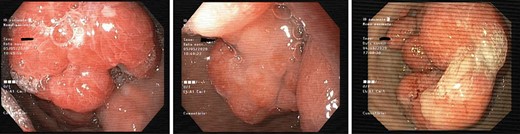

In April 2020, she needed hospitalization because of decompensated heart failure caused by symptomatic anaemia presented with an haemoglobin of 7,6 g/dl (hypochromic and microcytic) and a blood transfusion was needed. Thereupon, she was observed in a gastroenterology consultation to plan subsequent treatment: glycogenic acanthosis of the oesophagus, and multiple gastric and duodenal polyps were observed on EGD with very bulky polyps/conglomerate of polyps (50 mm) in the antrum with a very congestive, eroded surface and with some ulcers as observed in Fig. 1. It was considered endoscopic treatment but due to difficult access (if not impossible), probability of incomplete excision/recurrence and very high potential for complications it was consider inadequate an endoscopic approach.